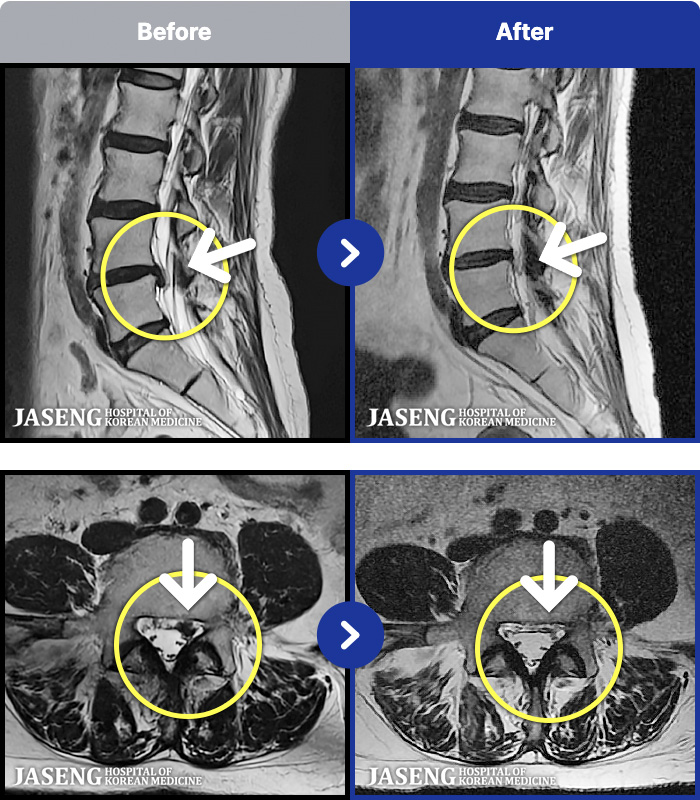

MRI ġ

54 MRI ũ ʸ Ȯϼ.

[Կñ:21.12.17~22.07.04]

[_㸮ũ] 㸮